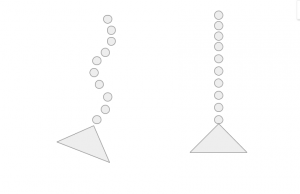

So why is it important to develop and maintain a neutral posture? Think of a spine and the way it moves like a broken pearl necklace like in the image below. In this picture, the pelvis is the triangle and the spine is the string of pearls. Without a stable pelvis, the bones in the spine follow the path of least resistance and move further into a curve like when you drag the end of a pearl necklace and all the beads follow the path of the first bead.

However, if you take the end of the pearl necklace and hold it with one hand and then pull the other end with the other hand the pearl necklace will straighten. The same thing will happen when you learn to find a neutral pelvis and work on lengthening your spine with an upright posture.